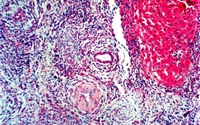

慢性排斥多发生在肝移植术后数月,有报道在移植后*个月就出现,呈渐进性加重,肝功能逐渐恶化,一般呈不可逆转性改变,是移植后期移植肝丧失功能的主要原因,也是影响患者长期健康存活的主要原因...